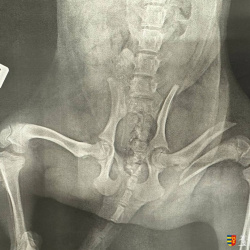

Az állatorvosi vizsgálat súlyos csontsérüléseket állapított meg. A kutyus jelenleg klinikán van, műtéti előkészület alatt – és mi bízunk benne, hogy egy új, boldog élet vár rá.